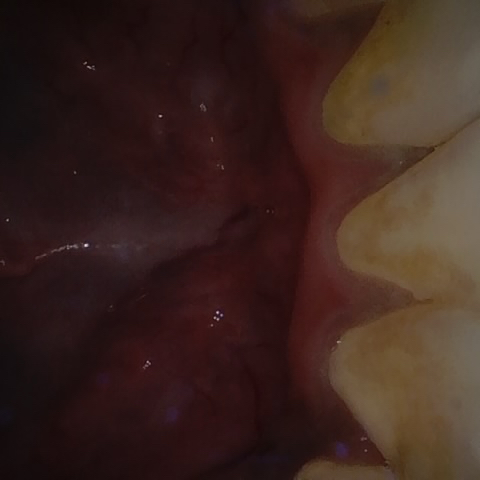

Annotated as "Good"

Original Image Rendering Image